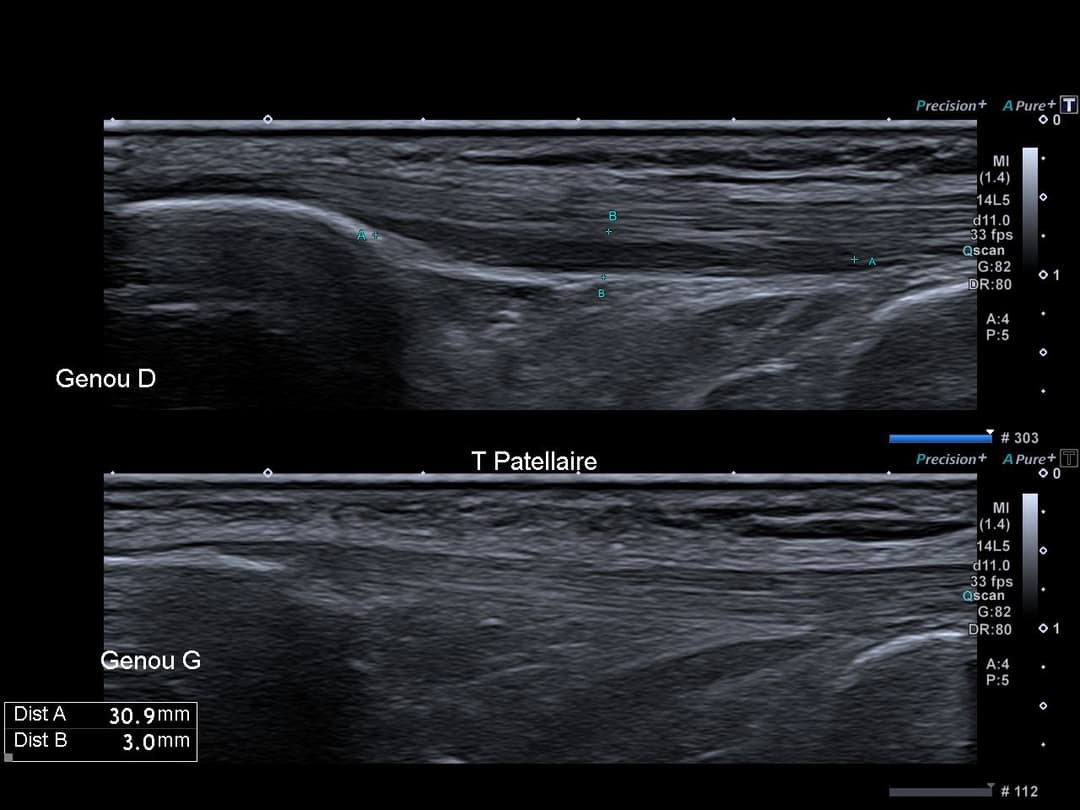

Échographie

Tendon patellaire présentant une plage de remaniement structurel modérément hypoéchogène, sans perte du caractère fibrillaire intéressant la face profonde du tendon sur 3 cm de grand axe, sans activité en Doppler.